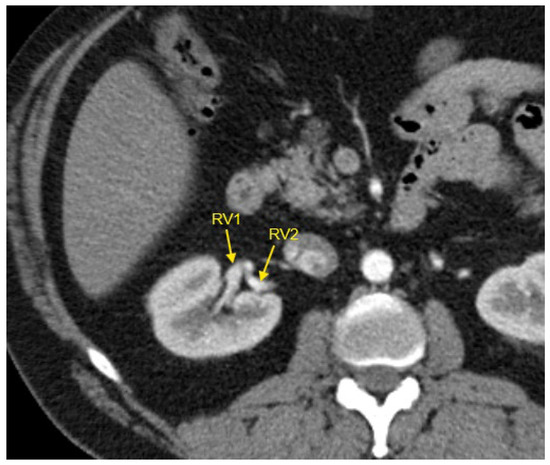

Figure 5. Contrast-enhanced CT imaging of a 44-year-old male hypertensive patient with difficult-to-control HTN revealed two renal veins in the right kidney, marked by the yellow arrows. CT—computed tomography; HTN—arterial hypertension; RV1—first renal vein; RV2—second renal vein.